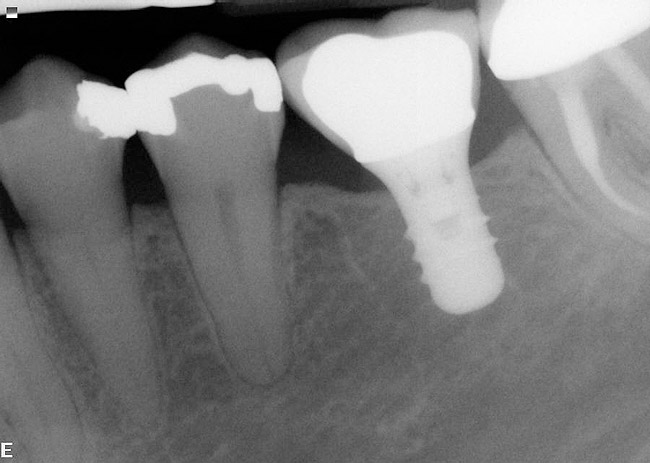

If the most crestal aspect of the interradicular bone is at least 3-mm-wide mesio-distally: A 2.2-mm-wide guide bur is drilled to the appropriate length, a guide pin is inserted, and a radiograph is taken (Figure 7). If necessary, the initial osteotomy is extended apically. A tapered osteotome is inserted into the osteotomy and moved mesio-distally and bucco-lingually to expand the osteotomy site. A 2.8-mm bur is used to prepare the osteotomy to depth, and a 2.8-mm-wide tapered osteotome is inserted in the osteotomy and once again utilized in mesio-distal and bucco-lingual directions to expand the osteotomy site. If the mesial and distal aspects of the interradicular bone are still intact at this point, a 3.5-mm bur is utilized to prepare the osteotomy to depth. A 3.5-mm-wide osteotome is inserted into the osteotomy and utilized in the manner already described. A decision is made as to whether to place a tapered implant with a 4.1-mm-wide base and a 6.5-mm-wide neck, or to use a 4.8-mm-wide bur and prepare the osteotomy to depth, in anticipation of placement of an implant with a 4.8-mm-wide parallel wall body and a 6.5-mm-wide platform. The chosen implant is inserted into the osteotomy (Figure 8), appropriate regenerative materials are placed, and the flaps are sutured. Following maturation of the regenerating hard tissues, the implant is ready for restoration (Figure 9). A radiograph taken 54 months after implant restoration demonstrates stability of the peri-implant crestal bone (Figure 10).

Case reports of these techniques can be seen in Figure 11 through Figure 19.

Using such techniques ensures predictable ideal implant positioning at the time of mandibular molar extraction. A recent publication documents 341 implants placed and restored utilizing the described protocols. Of these implants 204 were of a parallel wall design with a 6.5-mm-wide restorative platform, and 137 were of a tapered design with a 4.1-mm-wide base and a 6.5-mm-wide restorative platform. Two implants were lost prior to abutment connection, and no implants were lost in function, yielding a cumulative success rate of 99.1% with a mean time in function 30.7 months and a maximum time in function over 6 years.11